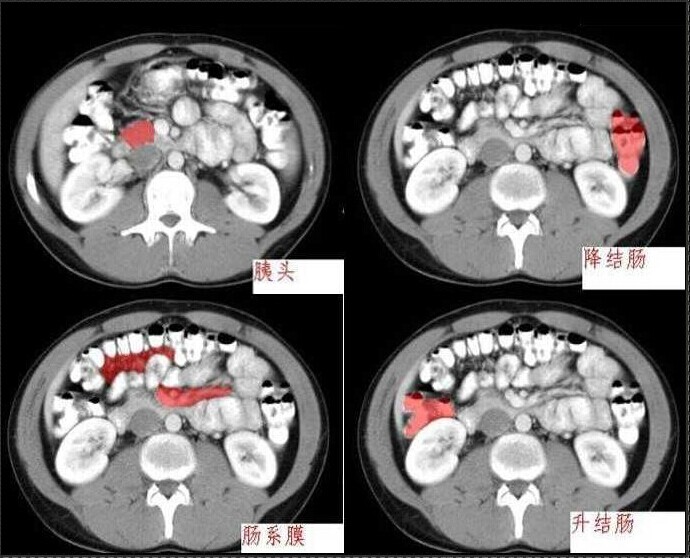

十分钟学会腹部CT解剖(多图)